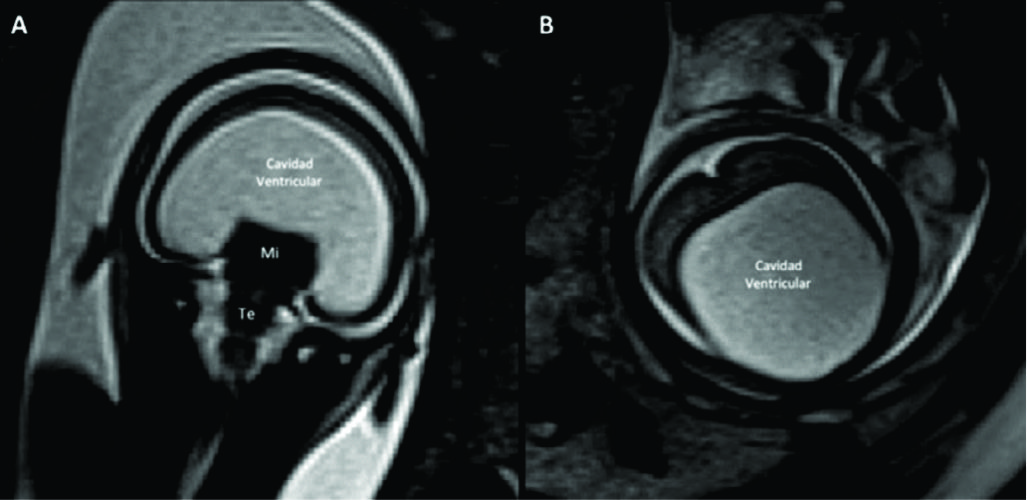

Figura 9

RM Fetal en Malformación de Fosa Posterior.

Se presentan 2 casos con diagnóstico de Dandy-Walker, ambos con malformación quística de la fosa posterior (è) comunicada con el IV ventrículo por alteración del desarrollo del vermis cerebeloso. En A y B imágenes sagital y axial de RMf realizada a las 27 semanas donde además se identifica dilatación del sistema ventricular supra-tentorial moderada. En el 2º caso (C y D) se observa una severa dilatación del sistema ventricular supra-tentorial con adelgazamiento del cuerpo calloso en un feto de 29 semanas de edad gestacional.

Te: Tronco encefálico

Ce: Cerebelo

Figura 10

RM Fetal en Malformación de Chiari.

Estudio realizado a las 29 semanas con diagnóstico ecográfico de mielomeningocele. En imagen coronal (A) se observa la severa dilatación del sistema ventricular supra-tentorial lo que se corrobora en la imagen axial (B) con una disposición colpocefálica de los ventrículos laterales (VL). En la imagen fetal sagital (C) se reconocen el cerebelo (Ce) y tronco encefálico (Te) sin identificarse claramente el IV ventrículo lo que indica una disminución de las dimensiones de la fosa posterior. En el mismo plano se observa el defecto de cierre posterior del tubo neural (è) con un saco de meningocele. La imagen axial a nivel de ese saco (D) muestra claramente el defecto espinal posterior (è) aunque sin observarse claramente el contenido neural del mismo.

Figura 11

RM Fetal Esquizencefalia bilateral.

Estudio de RM realizado en la semana 29 con diagnóstico ecográfico de esquizencefalia bilateral. En el corte axial (A) y coronal (B) se reconocen las clásicas hendiduras que vinculan el sistema ventricular con el espacio sub-aracnoideo de la convexidad en ambos hemisferios.

Las estructuras de línea media son normales así como también el tronco encefálico (Te) y el resto de las estructuras intra-craneanas.